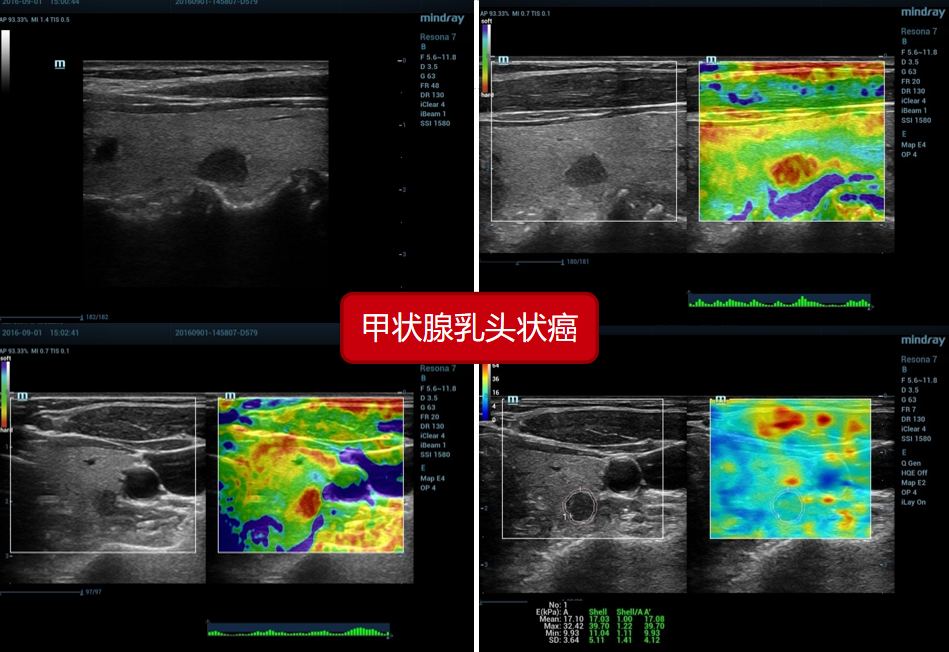

1、甲状腺乳头状癌(病例来源上海六院):

1、甲状腺乳头状癌(病例来源上海六院):